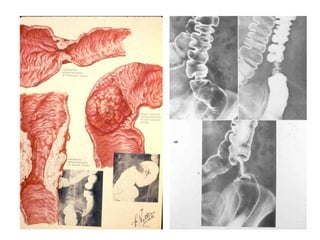

CARCINOMA

dạng polyp / dạng chồi sùi

dạng ổ loét – các nếp niêm mạc

dạng nhiễm cứng - linitis plastica

K dạ dày – khuyết hình lõi táo

K dạ dày dạng polyp

K dạ dày – hình ống nước do nhiễm cứng thành

Linitis plastica

K dạ dày dạng loét